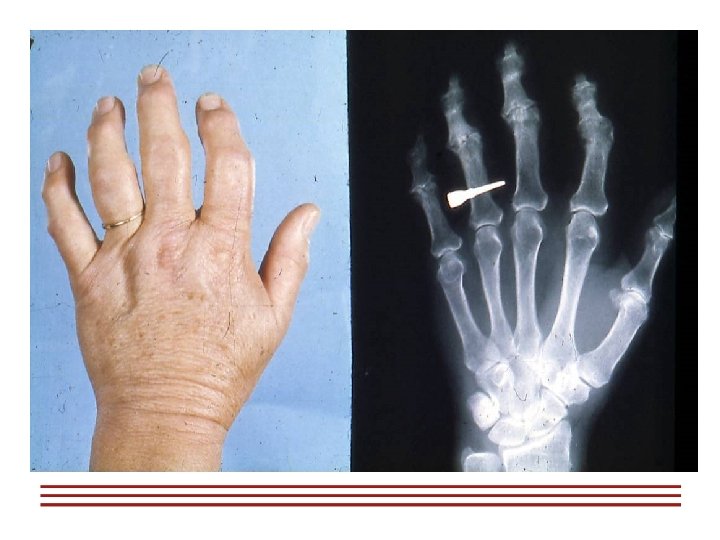

Наиболее часто остеоартроз поражает суставы üТазобедренный üКоленный üСуставы позвоночника üПлечевой сустав üМелкие суставы кистей рук и ног

Клинические проявления § Боль при физической нагрузке - Нестабильность - Остеофиты §Усиление болей к концу дня - Крепитация §Минимальная утренняя скованность (30 мин), усиливающаяся в покое §Уменьшение объема движений - Отек